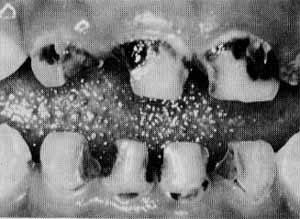

しかし、このバイ菌は、それ自体では虫歯をつくれません。口の中に食べ物が入ってはじめて、ミュータンス菌は虫歯をつくる能力をもつようになります。ミュータンス菌は、砂糖などの甘いものや、ごはん、パンなどを栄養源にして、ネバネバした、水に溶けにくい物質をつくります。これが歯の表面にべったりとくっつき、特殊な細菌膜をつくります。これを"プラーク(歯垢)"と呼んでいます。プラークをつくったミュータンス菌は、この膜を衣とし、その中で酸をつくります。歯を侵すのがこの酸です。このようにして、虫歯ができます。